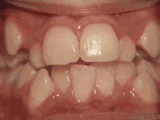

Openbite: Front teeth don't touch

openbite

Patient sucked her thumb as a young child. She started treatment at age thirteen. She had braces and a special appliance — called a crib — to retrain the tongue, for twenty-eight months. Now she can bite the lettuce out of a sandwich.